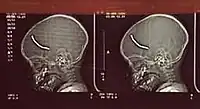

After his arrest following the bombings, Copeland told psychiatrists that he had started having sadomasochistic dreams when he was about twelve years old, including dreams or fantasies that he had been reincarnated as an SS officer with access to women as slaves.[19] He left school for a series of failed jobs, reportedly blaming immigrants for the difficult job market. Copeland became involved in petty crime, drinking, and drug abuse. His father was eventually able to get him a job as an engineer's assistant on the London Underground.[18]

Copeland's mental state was assessed at Broadmoor Hospital. He was diagnosed by five psychiatrists as having paranoid schizophrenia, while one diagnosed a personality disorder not serious enough to avoid a charge of murder. There was no dispute that he was mentally ill, but the extent of this, and whether he was unable to take responsibility for his actions, became a matter of contention. At the Old Bailey, Copeland's plea of guilty to manslaughter on the grounds of diminished responsibility was not accepted by the prosecution or jury.[14]